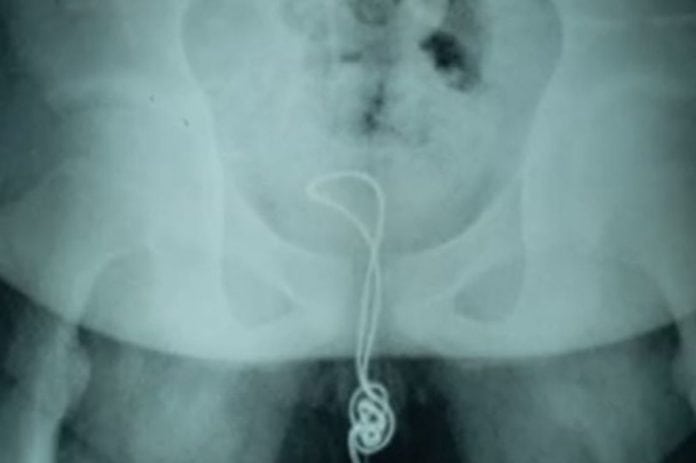

El chico de Linkou, China fue internado a un hospital el 4 de junio debido a los fuertes dolores que estaba experimentado en el pene y de encontrar sangre en su orina, acorde a Heilongjiang Metrópolis Channel.

Los doctores informaron que el cable se enredó y llegó hasta su vejiga.

Xu Liyan, doctora del Departamento de Urología, explicó que el cable en el pene del chico se había retorcido y enredado complicando las cosas.

Los expertos le aplicaron lubricante para extraer el cable.

Sin embargo, el nudo era tan grande que no pasaba por la uretra y esto podría generarle lesiones al chico.

Después, decidieron hacer una incisión en el punto donde el cable estaba anudado, antes de quitarlo.